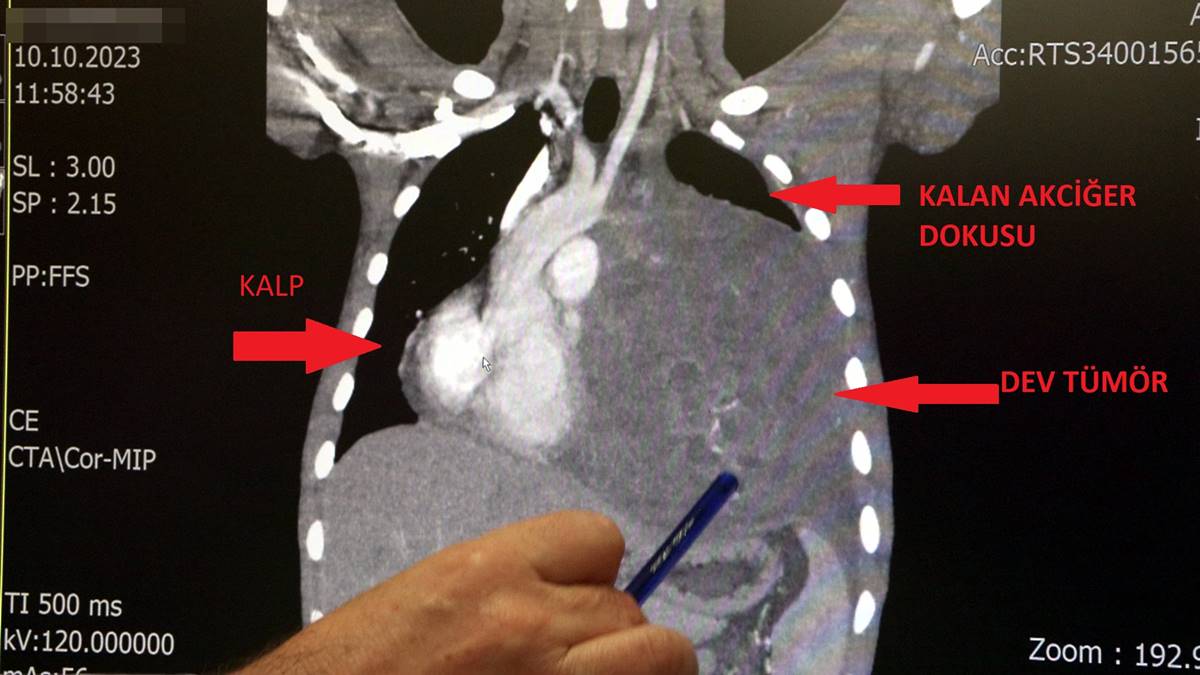

Sol akciğerinin yüzde seksenini kağıt gibi ezen, kalbini göğüs duvarında 12 santim sağa kaydıran ve hem kalbe hem beyne giden ana damarlara baskı yapan 6.5 kilo ağırlığındaki dev tümör, Koşuyolu Yüksek İhtisas Eğitim ve Araştırma Hastanesi Göğüs ve Kalp Damar Cerrahisi ekiplerinin birlikte girdiği operasyonla başarılı şekilde çıkarıldı.

Operasyon sırasında Burak Aktaş'ın kalbi normal yerine çekildi, sol akciğerin üst lobu alındı, ezilen alt lobu ise anestezi ekipleri tarafından pozitif basınçla yeniden şişirildi. Ameliyatı gerçekleştiren ekipten Prof. Dr. Erdal Taşçı, Aktaş’ın göğüs boşluğunun neredeyse tamamını kaplayan 6,5 kiloluk tümörün teratom (eski Yunancada 'canavar tümör') türlerinden biri olduğunu ve embriyonik hücrelerden kaynaklandığını kaydetti.

2 ay arayla yapılan tetkiklerinde ve arada cerrahi öncesi küçültme amaçlı kemoterapi almasına rağmen, portakal büyüklüğündeki tümör, irice bir karpuz büyüklüğüne, yaklaşık 6 kilo 300 grama kadar ulaşıyor. Göğüs boşluğunda kemik kafesi içinde olduğu için, itebileceği iki organ var; biri kalp, diğeri de akciğerler.

Soldan sağa doğru büyüdüğü için kalbi tamamen göğüs boşluğunun sağ tarafına itmiş ve kalbe giren ve kalpten çıkan bütün büyük damarları da yer değiştirmenin etkisiyle bükülmüş durumdaydı. Bu nedenle vücuduna yeterince kan gitmiyordu. Ağustos ayının başında portakal büyüklüğündeyken kitle Eylül sonuna irice bir kavun, Ekim ayına geldiğimizde ise bir karpuz büyüklüğüne ulaştığı için, kitlenin büyüme hızı bizi acilen ameliyat yapmaya yöneltti. Yaklaşık 8-10 kat hacimsel olarak artmıştı.

Sol akciğer tamamen ezilmiş ve kağıt haldeydi, alt lobu anestezi ekibimiz yüksek basınç uygulayarak tekrar şişirdi. Çok fazla vaktimiz yoktu, kitle basısından dolayı yaşamla bağdaşmayacağından dolayı hızlı hareket etmek zorundaydık. Bize geldikten üç gün sonra hemen ameliyata aldık çünkü tümörden ziyade onun yaptığı baskıdan kaynaklı hayati riski vardı."

"Ama bu hastada yaklaşık 12-13 s santimlik kalbin alt ucununu yer değiştirmesi ve kalbe giren çıkan bütün damarlar bükülüp kan akımı bozulmuştu. Kalp Damar Cerrahisi ekibi de bizimle beraber ameliyata girdi. Sol akciğerin üst lobu artık geri dönüşümsüz olarak ezildiği için çıkarmak zorunda kaldık.

Kalbi tekrar eski pozisyonuna getirdik. Ameliyat sonrası çok çabuk toparladı. Koşuyolu ailesi olarak böyle büyük bir vakanın altından başarıyla çıktığımız için de ayrıca çok gururluyuz. Bundan sonra onkolog arkadaşlarımız hastamızın yaşamına çok olumlu dokunuşlar yapacak.